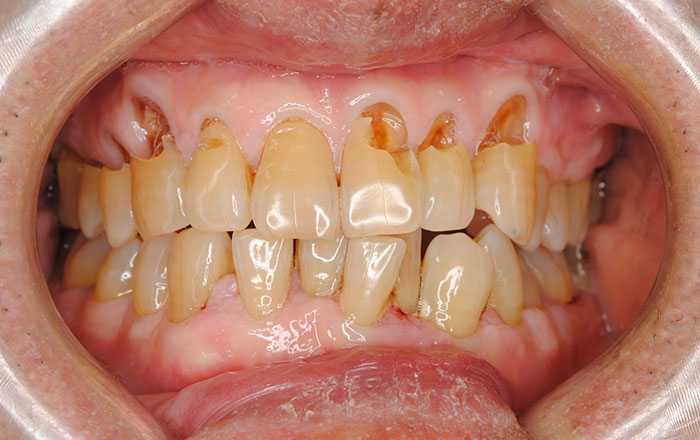

・歯の磨耗により歯がしみる、かける

・歯が割れて噛むと痛い

・噛み合わせが深くなり被せ物が取れやすい

先ほどは、身体に起こる症状をお伝えしましたが、お口の中にも症状が出ます。

お口の中の症状は以下の内容です。

①頬の内側、舌の横に付く歯の痕

②上顎下顎にできる骨隆起

③ほっぺの内側に歯の跡がつく

このような症状があると歯ぎしり、食いしばりをしている可能性があります。